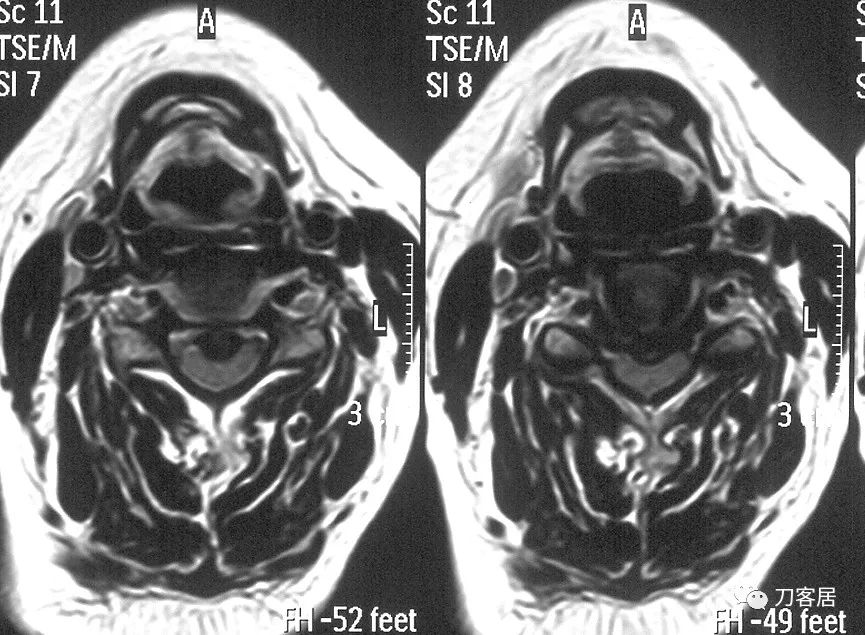

图4. 颈椎MRI横截面提示颈4-5椎间盘突出,椎管狭窄,脊髓受压